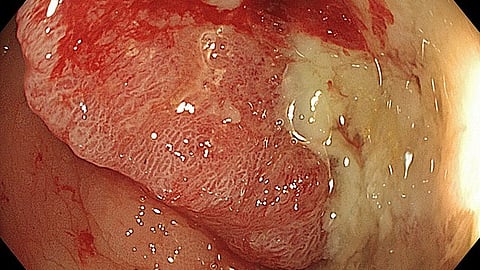

Guryanova and colleagues decided to investigate the role of clonal hematopoiesis in colitis-associated colon cancer (CAC). Inflammatory bowel disease, including ulcerative colitis and Crohn’s disease, is a well-known risk factor for colon cancer, and clonal hematopoiesis is prevalent in both IBD and colon cancer patients.

The researchers generated mice with clonal hematopoiesis by transplanting them with blood stem cells lacking one copy of Dnmt3a, the most frequently mutated gene in clonal hematopoiesis patients. The mice were then treated with drugs that induce the development of CAC. Guryanova’s team found that CAC occurred more frequently, and developed more rapidly, in mice with clonal hematopoiesis, resulting in larger tumors with a worse histopathology.